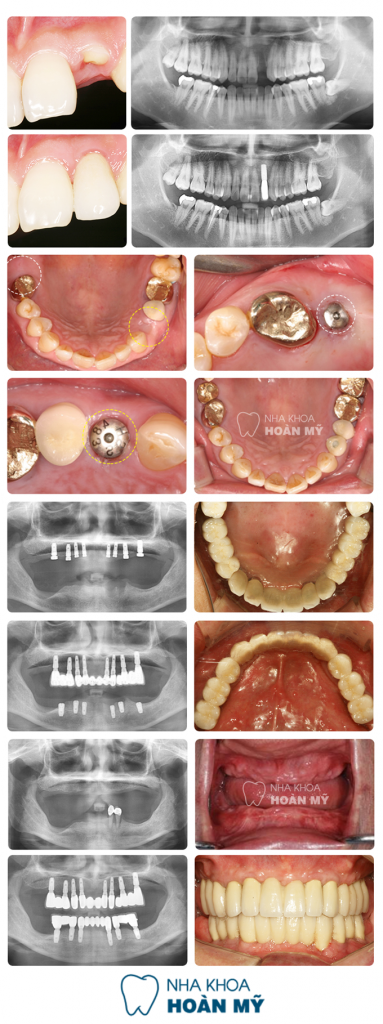

Top Những biện pháp Cấy Răng hiệu quả nhất năm 2017 - ảnh 3Những ca cấy răng thành công tại Nha khoa Paris bằng công nghệ hiện đại

Hiệu quả thực tế đạt được từ công nghệ này đã được kiểm chứng rõ ràng và chắc chắn qua hàng ngàn ca phục hình mất răng, thiếu răng tại Nha khoa Paris. (Xem chi tiết các ca điều trị này TẠI ĐÂY).